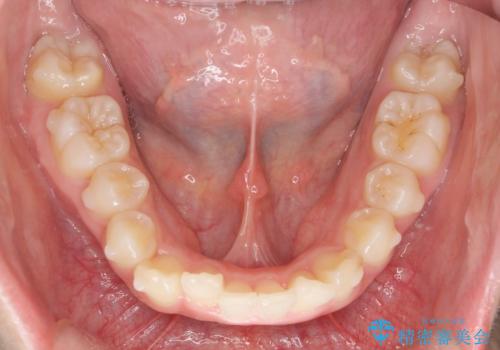

- 高校時代の吹奏楽の部活でサクソフォン(アルト)を担当、「一生懸命練習をしすぎて気づいたら歯並びが悪くなっていた。矯正治療を受けたい!。」

とマウスピース矯正を希望され来院されました。

歯列の乱れが大きく難易度が高いため、

・治療期間の長期化が予想されること

・マウスピースで治り切らない場合ワイヤー矯正に変更すること

をご理解いただいた上でマウスピース矯正治療を計画します。